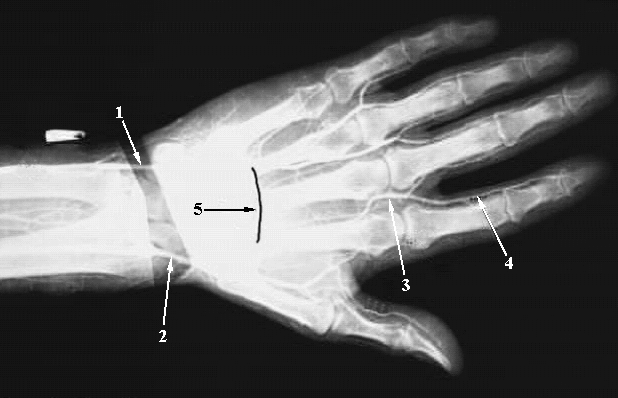

Upper Limbs:Hand Angiogram:

1. Ulnar Artery

2. Radila Artery

3. Common Palmar Digital Artery

4. Proper Palmar Digital Artery

5. Deep Palmar Arch.